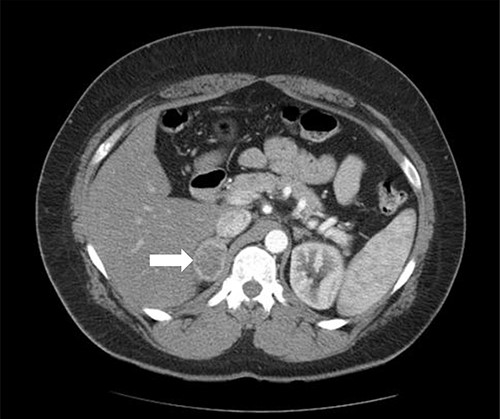

A 37-year-old male, with a BMI of 42 kg/m2, dyslipidemia HTN and gout, presented to our private clinic with progressive weight gain. He also reported an incidental 1.6 cm left adrenal mass on a CECT of the abdomen, which was done in 2014. A repeated CECT showed a larger left adrenal mass of 5 cm, which was lobulated and suggestive of atypical lipid-poor adenoma (Fig. 3). A biochemical workup showed normal serum metanephrine of 50 ng/l (reference <90), normal serum normetanephrines of 90 ng/l (reference <129) and serum morning cortisol of 250 nmol/l. Considering the increasing size of the left adrenal gland and the patient's concerns about it, a LSG combined with LLA was offered to the patient for weight management and diagnosis confirmation of the left adrenal gland.

Axial CT of the abdomen showing the left adrenal mass in Patient 3 (white arrow).